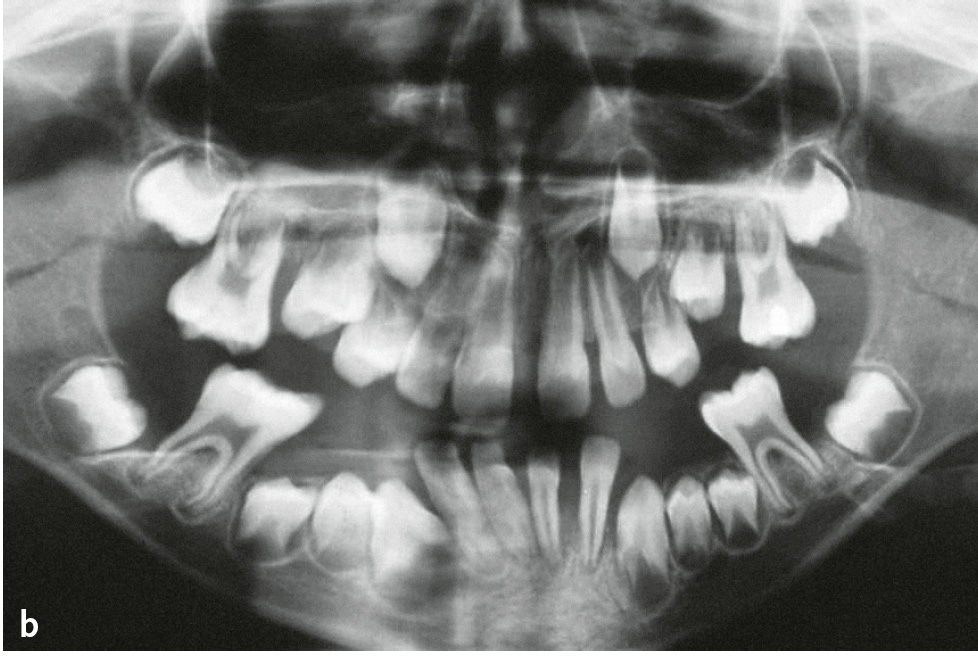

Das Papillon-Lefèvre-Syndrom (PLS; Keratosis palmoplantaris – Periodontopathie; ORPHA678/ICD-10: Q82.8) beschreibt seltene, autosomal-rezessiv erbliche Mutationen des Kathepsin-C-Gens, die zur Inaktivität dieser Cysteinprotease führen. Kathepsin C aktiviert die Serinproteasen (Elastase, Kathepsin G, Protease 3, Neutrophilen-Serinprotease 4) der neutrophilen Granulozyten. Damit ist die erste Linie der parodontalen Infektabwehr beeinträchtigt. Die charakteristischen Symptome sind palmoplantare Hyperkeratosen mit einer bereits im Milchgebiss einsetzenden und sehr rasch verlaufenden Parodontitis (Abb. 1a bis d). Allerdings sind auch atypische Verläufe bekannt, bei denen entweder nur Hautsymptome oder nur die im Milchgebiss einsetzende und rasch verlaufende Parodontitis auftreten6. Die Häufigkeit beträgt 1–4:1.000.000. Untersuchungen der neutrophilen Granulozyten haben in manchen Fällen gestörte Zellfunktionen wie eine verminderte Motilität, Chemotaxis und Phagozytose sowie eine verminderte Produktion von Sauerstoffradikalen gezeigt, die sich in manchen Fällen nach der therapeutischen Intervention normalisierten. In der subgingivalen Plaque werden zumeist vermehrt anaerobe gramnegative Keime und vor allem Aggregatibacter actinomycetemcomitans nachgewiesen.

Abb. 1a bis d Männlicher Patient mit Papillon-Lefèvre-Syndrom: a) klinische Ansicht im Alter von 7 Jahren und 9 Monaten (vor Therapie: ausgeprägte Mobilität der Unterkieferschneidezähne, Sondierungstiefen an ersten Molaren und Unterkieferschneidezähnen von 9 bis 15 mm); b) Panoramaschichtaufnahme; Hyperkeratosen an c) Hand- und d) Fußflächen (Abbildungen aus Kugel et al. 20015).

Die Symptomatik umfasst über die palmoplantaren Hyperkeratosen und die im Milchgebiss einsetzende und rasch verlaufende Parodontitis hinaus psoriasiforme Hyperkeratosen an Ellenbogen und Knien, Nageldystrophie, Mineralisationen der Dura mater und gehäufte bakterielle Infekte.

Die Therapie der Hautveränderungen erfolgt zum Teil mit oralen Retinoiden, aber auch urathaltigen Salben. Eine erfolgreiche Therapie der Parodontitis ist möglich. Der Erfolg scheint von verschiedenen Faktoren abzuhängen: möglichst frühzeitiger Beginn (ggf. schon im Milchgebiss), Elimination von A. actinomycetemcomitans und engmaschige professionelle Nachsorge (Abb. 1e und f)7.